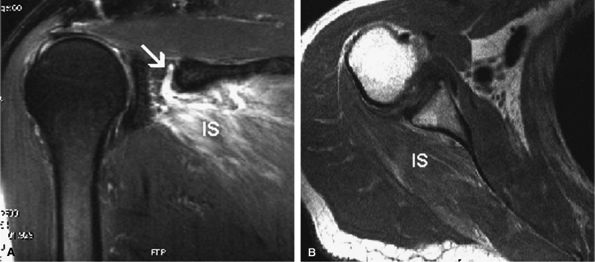

![]() |

FIGURE 12.7 ● Suprascapular nerve syndrome secondary to a ganglion. Oblique coronal (A) and sagittal (B) fat-suppressed T2-weighted images demonstrate a large cystic lesion occupying the suprascapular incisura and spinoglenoid notch in keeping with a ganglion (arrow). Abnormal T2 hyperintensity consistent with denervation edema involving the infraspinatus muscle (IS) is noted.